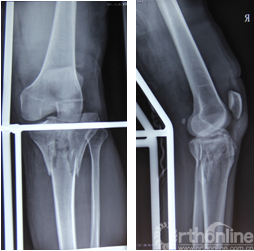

陈**43岁男性患者,因高处坠落伤致右膝肿痛伴活动受限3天入院。入院后完善相关影像学检查后,诊断为“右胫骨平台骨折(SchatzkerⅥ型)”。

术前平片